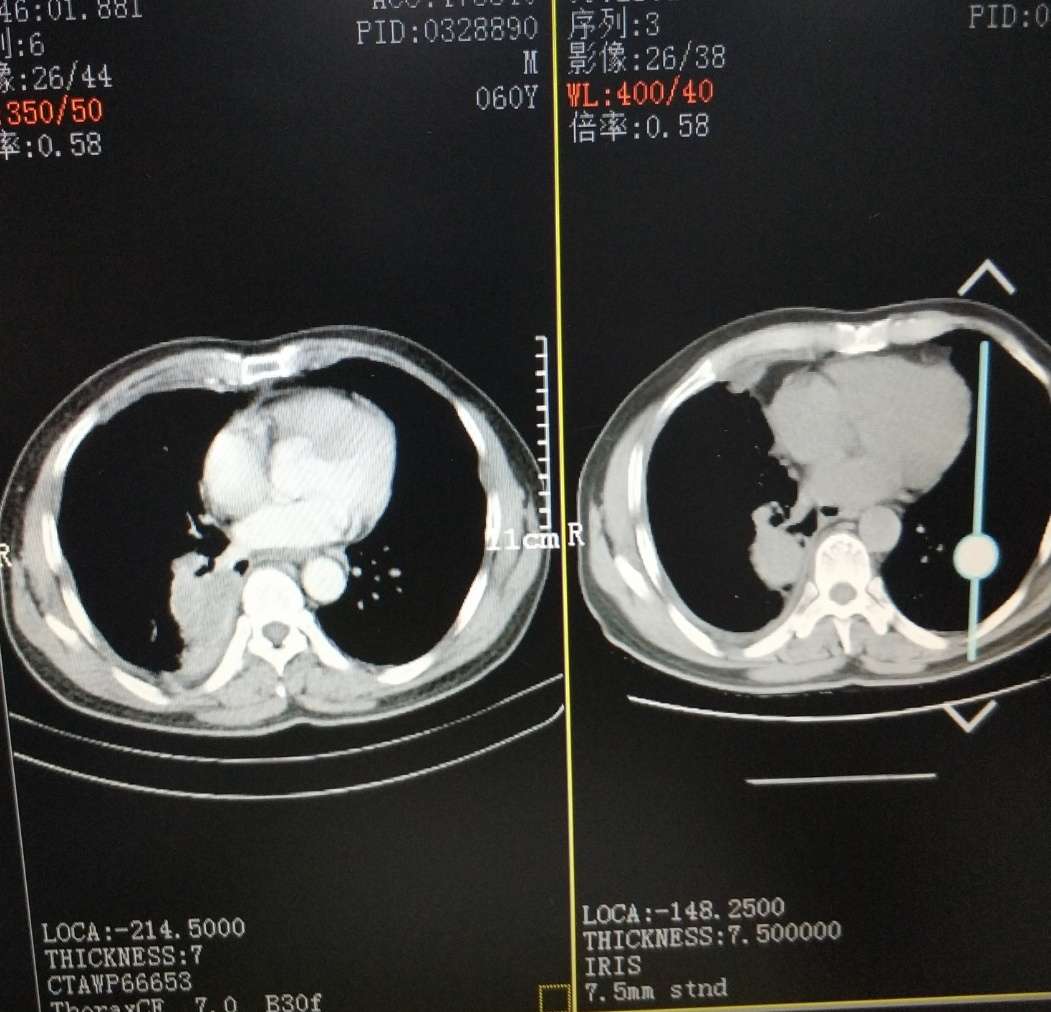

晚上好,我爸爸胸水控制不住周一转到浙二滨江呼吸科就诊,19突变易瑞沙吃2个月时间,昨天CT做出来医生说相比较上次9月18日肿瘤还大了而且有新的,医生建议易瑞沙可能耐药才2个月时间,易瑞沙没效果,前天还咳血了15ml鲜红色,今天中午又咳血了一口,医生建议化疗药卡铂+培美曲塞,或者做其他有靶向药的全基因检测,这两天开始吃善存维生素片,+白蛋白偏低自费打了白蛋白针和香菇多糖,我这两天压力很大,不知道该怎么办好,希望能够得到您的一些建议,谢谢,谢谢